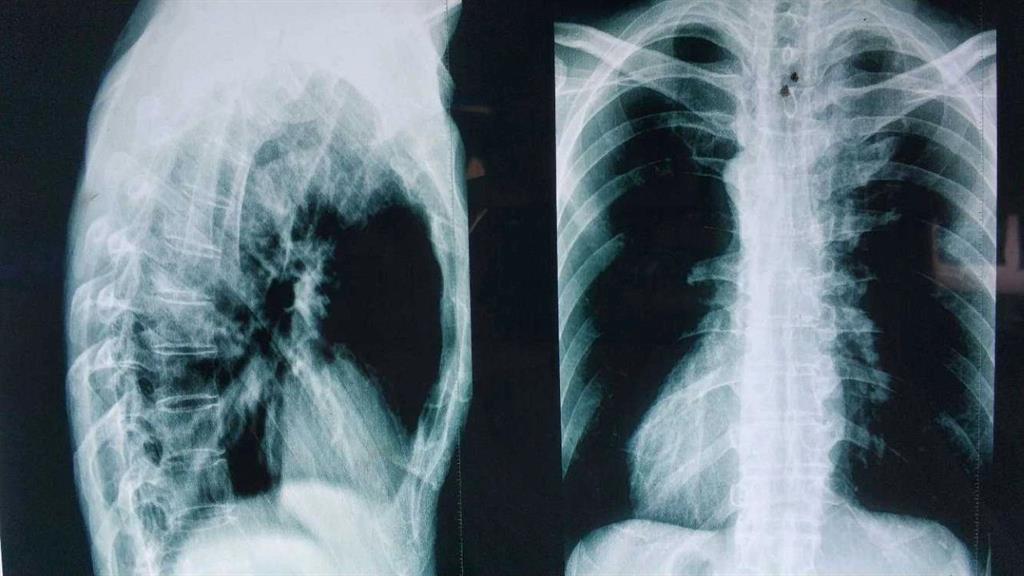

“HLA-B27陰性……從驗(yàn)血報(bào)告來(lái)看是正常的……X光……也沒什么問(wèn)題,這邊建議你再去拍個(gè)髖關(guān)節(jié)的核磁共振。”醫(yī)生轉(zhuǎn)過(guò)身對(duì)著男孩說(shuō)。

“這是之前拍的磁共振的片子。”

醫(yī)生接過(guò)片子對(duì)著燈源看了看。

“小伙子!因?yàn)槟阏f(shuō)拍片是為了確實(shí)是否為強(qiáng)直性脊柱炎,我們剛才在拍片的時(shí)候發(fā)現(xiàn)按照那邊醫(yī)生要求的部位拍攝還是看不到病癥點(diǎn),所以我們給你拍了兩次,你到時(shí)候給醫(yī)生看的時(shí)候都給他看。”

“確實(shí)挺快的,那邊的醫(yī)生給我拍了兩次你看看。”

“這種拍多了就只是花錢多而已。”男孩沒有說(shuō)話。

醫(yī)生對(duì)著拍好的片子來(lái)來(lái)回回看了好幾遍,男孩就一直站在他邊上,他知道醫(yī)生接下來(lái)說(shuō)的話將決定自己的一生。